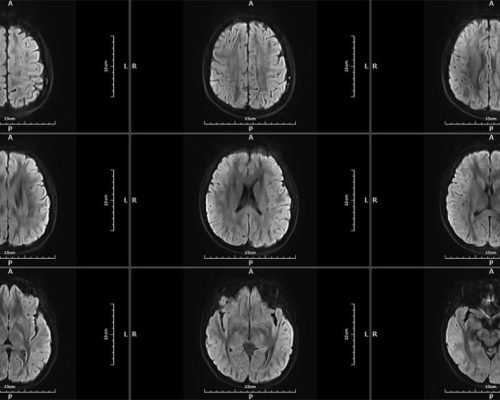

MICA represents the pinnacle of innovation in 1.5T whole-body MRI systems, delivering image quality rivaling 3T systems through its unique High-Temperature Superconducting (HTS) RF coil technology.

MICA is the result of our commitment to develop the world’s highest performing 1.5T whole body MRI system with integrated superconducting RF coil. The superb image quality targeting 3T system performance level is made possible with the unique High-Temperature Superconducing (HTS) RF coils patented by Time Medical Systems.

High-performance gradient system enables faster scanning and sharper images, ideal for advanced neurological and musculoskeletal applications.